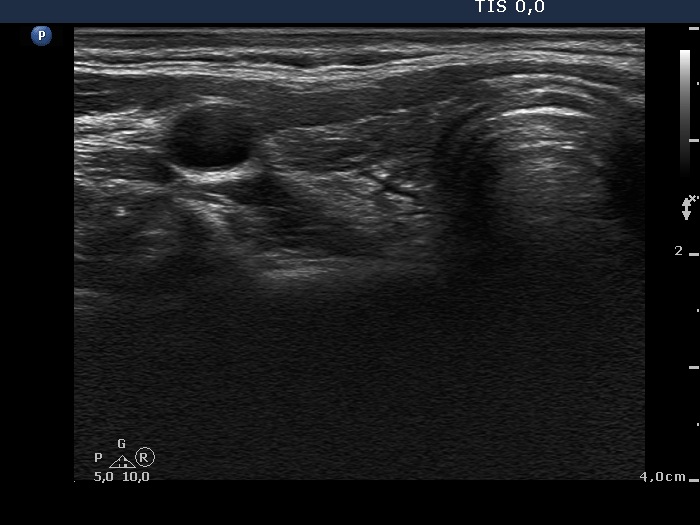

One year after radioiodine therapy (third row):

Clinical presentation: the patient had no complaints.

Palpation: the thyroid could not be palpated.

Functional state: mild hypothyroidism on daily 112.5 microgram levo-tiroxine (TSH-level 5.11 mIU/L).

Ultrasonography: the thyroids were hypoechogenic and presented extensive fibrosis. The size of the lobes decreased significantly. The thyroid presented no and decreased vascularization, right and left lobe, respectively.

Suggestion to increase the dose of levo-tiroxine to daily 125 microgram.